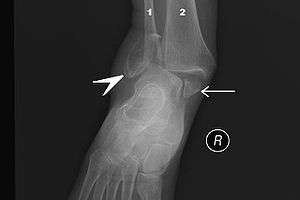

Bimalleolar fracture and right ankle dislocation on X-ray (anteroposterior). Both the end of the fibula (1) and the tibia (2) are broken and the malleolar fragments (arrow: medial malleolus, arrowhead: lateral malleolus) are displaced. | |

On X-rays, there can be a fracture of the medial malleolus, the lateral malleolus, or of the anterior/posterior margin of the distal tibia. The posterior margin (known as the posterior malleolus) is much more frequently injured than the anterior aspect of the distal tibia. If both the lateral and medial malleoli are broken, this is called a bimalleolar fracture (some of them are called Pott's fractures). If the posterior malleolus is also fractured, this is called a trimalleolar fracture.